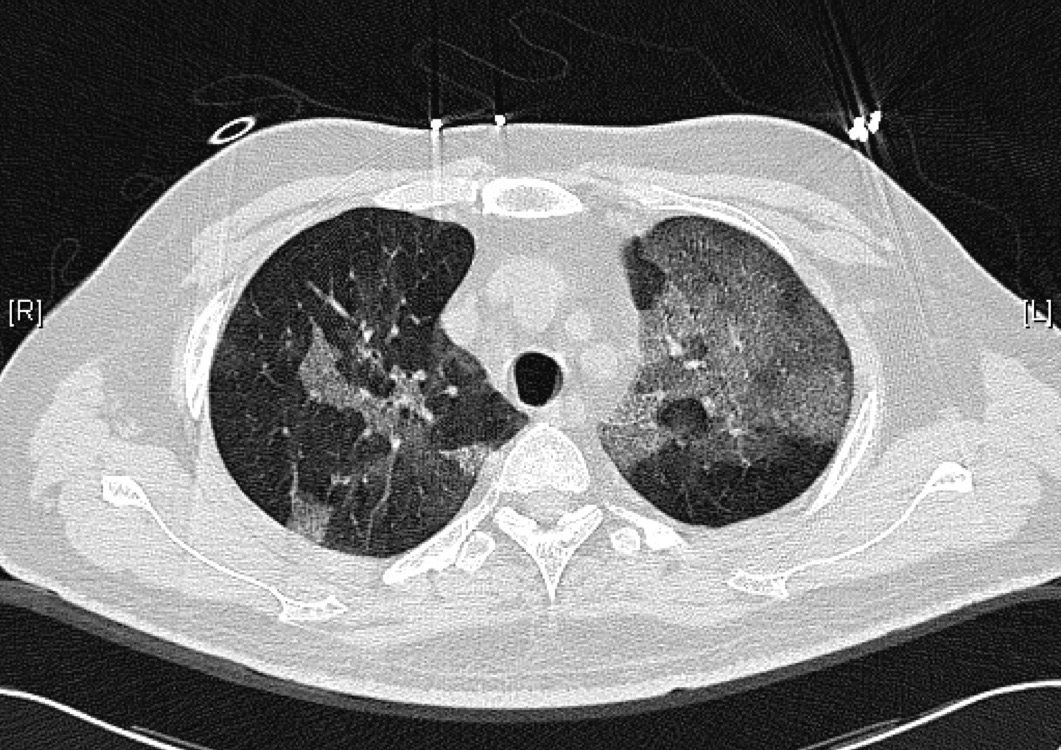

Below are his chest X-ray and a single cut of the CT thorax performed during the early stages of his illness.

The rest of the CT thorax essentially showed the same findings: ground glass changes throughout all lobes of his lungs.